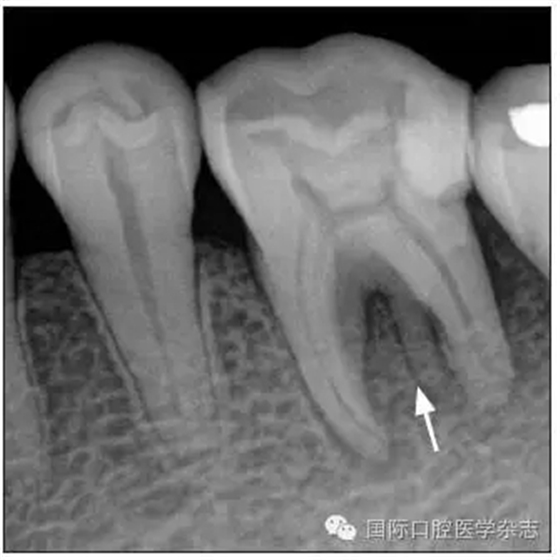

患牙被診斷為根尖周炎,鹽酸甲哌卡因/腎上腺素注射液(斯康杜尼)麻醉后,橡皮障隔濕,開髓,找到3個根管口。根尖片可見牙槽骨內(nèi)有一個根樣影像(圖4),故再次尋找根管口,但未找到。

圖4根樣釉珠

Fig 4 Root-like enamel pearl